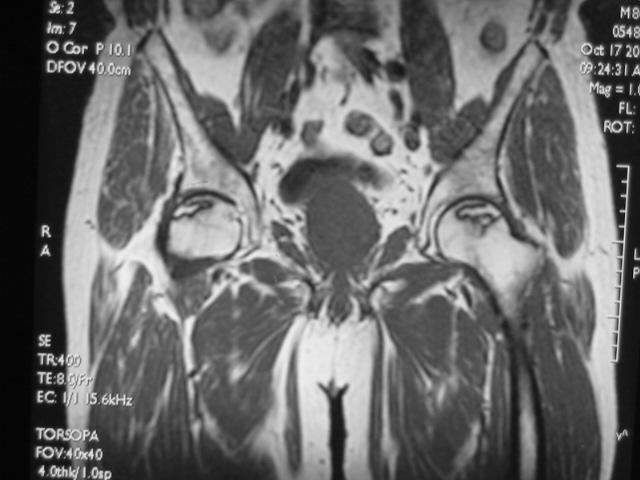

Ⅱ期

髋关节间隙正常,股骨头光整、不变形。

在T1W上,股骨头前上部负重区,有硬化缘围绕较低、不均匀信号的新月形坏死区。

在T2W上,病灶为星月形高信号区。

在X线平片上,股骨头负重区内可见高密度的硬化区,内可伴有小囊样改变。